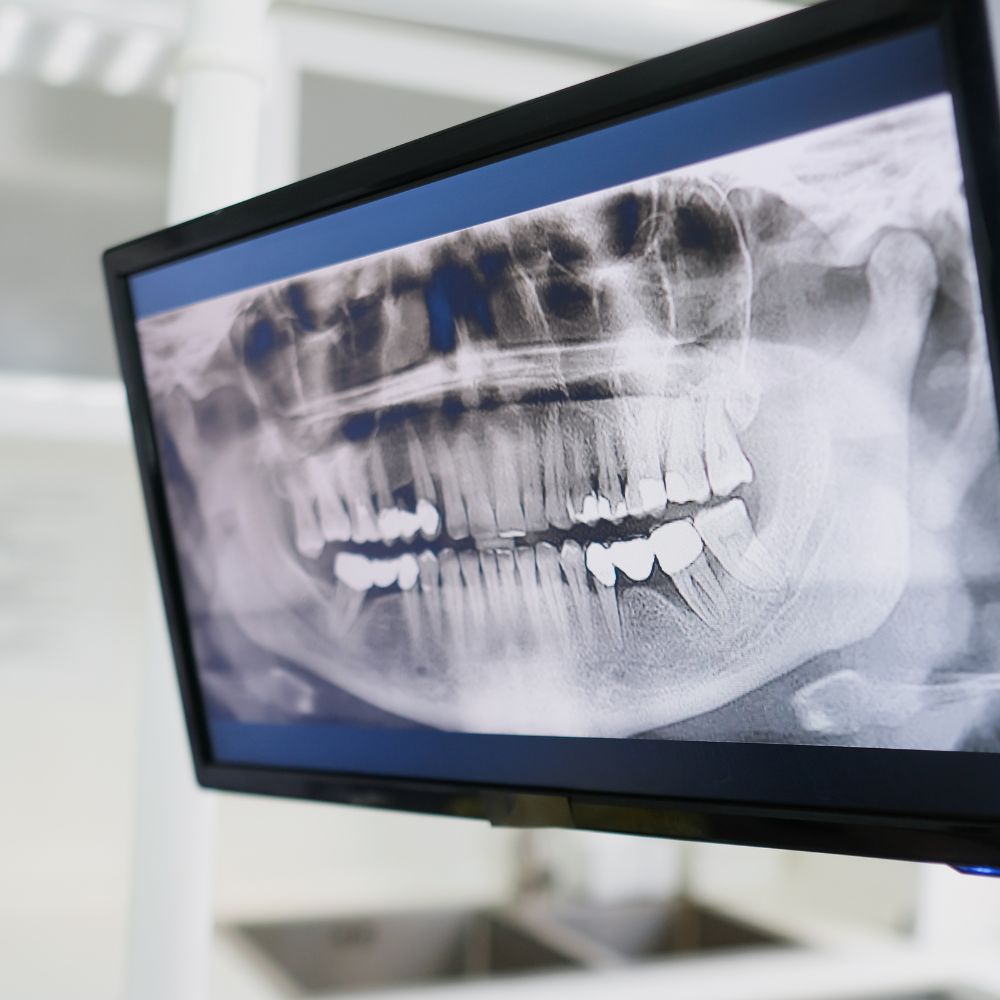

Les radiographies dentaires utilisent des rayons X, mais les doses sont extrêmement faibles. En fait, une radiographie dentaire correspond à peu près à la quantité de rayonnement que l’on reçoit naturellement lors d’un voyage en avion de deux heures. De plus, les appareils modernes sont conçus pour limiter au maximum l’exposition. Le dentiste utilise parfois un tablier de protection en plomb pour rassurer et protéger le patient. Ces examens sont indispensables pour voir ce qui ne se voit pas à l’œil nu : caries cachées, infections sous une dent, fractures, dents de sagesse coincées, état de l’os… Il ne faut donc pas craindre une radio dentaire. Elle permet au dentiste de poser un diagnostic sûr et d’éviter des traitements inutiles ou tardifs.